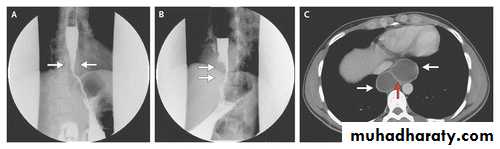

Diaphragmatic ruptureDiaphragmatic rupture

Diaphragmatic rupture

Liver herniation in right side